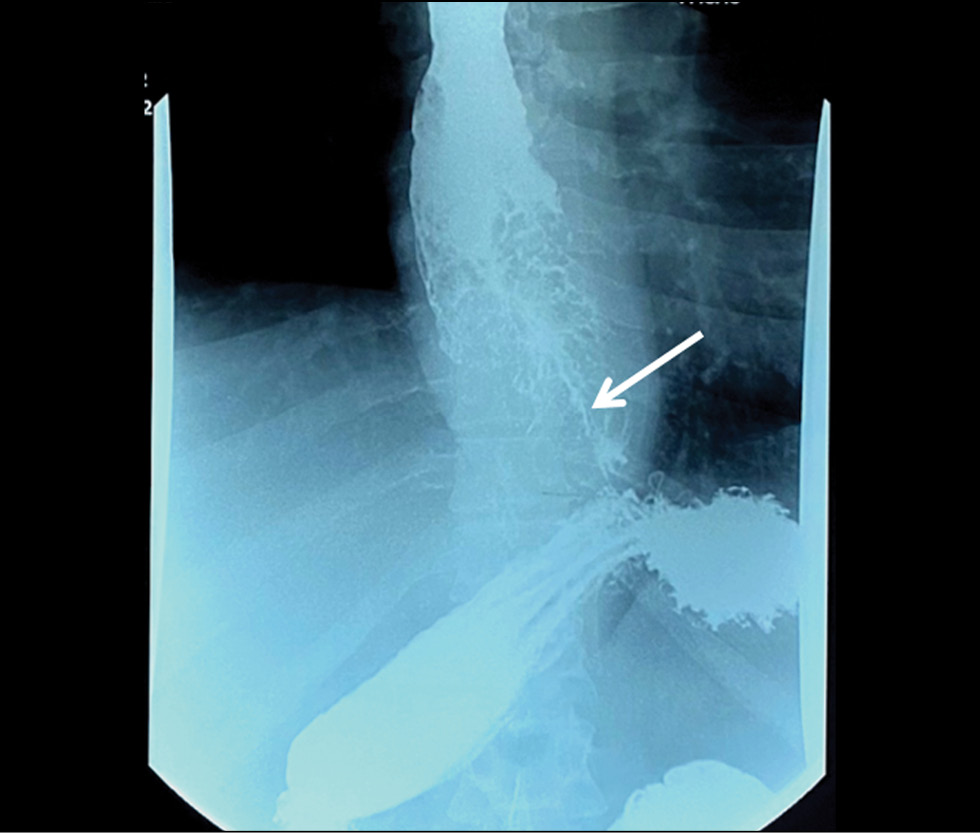

Structural gray matter changes in primary progressive aphasia variants

BACKGROUND: Primary progressive aphasia is a rare neurodegenerative disease with high clinical, genetic, and pathomorphological heterogeneity that greatly complicates its diagnosis. Voxel-based morphometry can be used to objectively assess structural gray matter changes and determine atrophy patterns in variants of primary progressive aphasia, which can improve the diagnosis and our understanding of its pathogenesis.

AIMS: This study aimed to evaluate the patterns of atrophy in each of the primary progressive aphasia variants in comparison with the control group.

MATERIALS AND METHODS: Patients diagnosed with one of the primary progressive aphasia variants, established in accordance with the current diagnostic criteria, were included in the main group. The control group consisted of healthy volunteers without any neurological symptoms or structural brain changes. All participants underwent brain magnetic resonance imaging. The obtained images were processed and used for voxel-based morphometry, which was performed by comparing the gray matter volume between each of the primary progressive aphasia variants and the control group. The study was adjusted for the sex, age, and intracranial volume of the participants.

RESULTS: The study enrolled 25 patients with nonfluent, 11 with semantic, and 9 with logopenic variants of primary progressive aphasia, as well as 20 healthy volunteers. Voxel-based morphometry showed a specific atrophy pattern in each of the variants of primary progressive aphasia, with predominant involvement of the frontal and insular lobes in nonfluent, temporal lobe and hippocampus in semantic, and a more diffuse frontotemporal pattern in logopenic variants.

CONCLUSIONS: The study revealed gray matter atrophy patterns specific to each variant of primary progressive aphasia. The obtained results mainly correspond to the clinical presentations of the disease. Moreover, some findings (e.g., absence of the posterior perisylvian atrophy and reduced motor cortex volume in the logopenic variant, atrophy of the orbitofrontal cortex and cerebellum in the nonfluent variant, and premotor cortex, precentral, and inferior frontal gyrus degeneration in the semantic variant) do not correlate with the usual understanding of primary progressive aphasia pathogenesis and require further study.

467-480